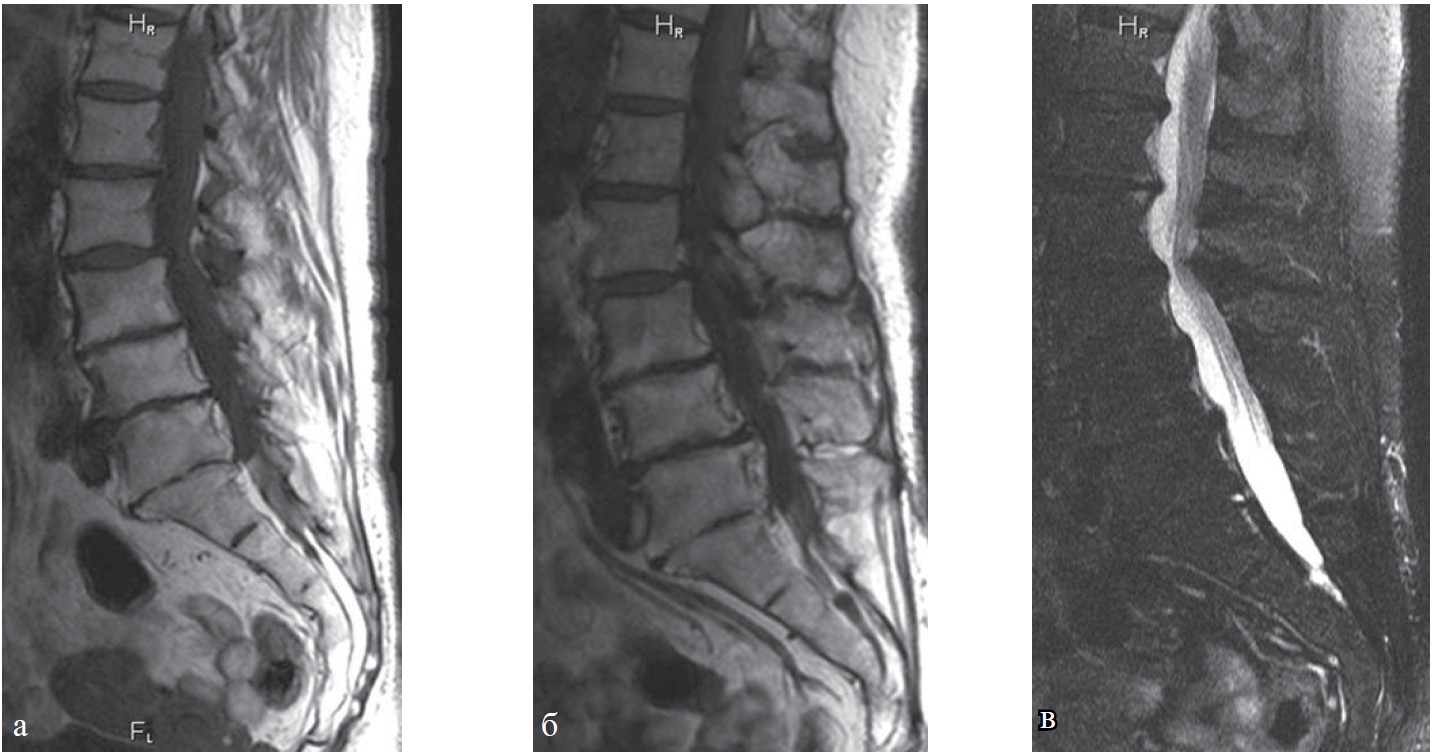

В 1 группу были отнесены 376 пациентов, у которых были выявлены начальные проявления остеохондроза позвоночника (I стадия), дискоз I стадии, дегенерация диска без выпячивания, без изменений со стороны межпозвоночных суставов, плотности и структуры кости позвонка (рис. 1-4), спондилолистез I степени без признаков дегенеративного сужения позвоночного канала, стабильность позвоночных двигательных сегментов при функциональных пробах.

Рис. 2. Рентенография шейного отдела позвоночника, та же пациентка: а — прямая проекция; б — боковая, в — в положении максимального сгибания; г — в положении максимального разгибания. Определяются нарушение статики, начальные явления остеохондроза шейного отдела позвоночника (I степень).

Рис. 3. КТ поясничного отдела позвоночника, та же пациентка: а, б — аксиальная плоскость;

в, г — сагиттальная плоскость. Определяются остеохондроз поясничного отдела позвоночника I ст., спондилоартроз, передний спондилолистез позвонка L3 I ст.

Рис. 4. МРТ грудного отдела позвоночника, та же пациентка: а -Т1-ВИ; б, г, д — Т2-ВИ; в — Т2-ВИ с жироподавлением. Определяется остеохондроз грудного отдела позвоночника I ст., умеренное снижение высоты тел ТН6—ТН9, грыжи Шморля в краниальных и каудальных пластинках тел ТН6-ТН10, признаки перенесенной болезни Шейермана-Мау.